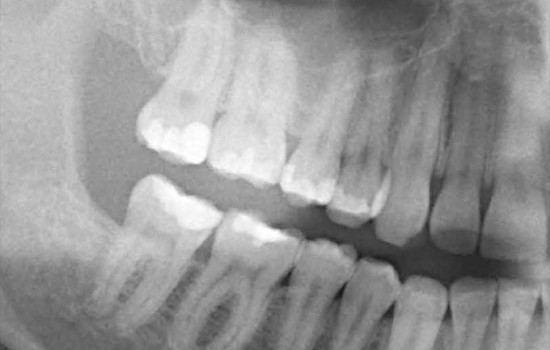

Digitales Röntgen

Weniger Belastung durch modernste Technik

In unserer Praxis in Norderstedt bei Hamburg werden ausschließlich digitale Röntgenbilder erstellt.

Schnellere Diagnosen, bessere Kommunikation mit dem überweisenden Kollegen und vor allem die Reduktion der Strahlenbelastung um bis zu 80% für den Patienten sind die entscheidenden Vorteile.

Es fallen keine umweltschädlichen Entwicklungschemikalien an! Statt eines Films, der von den Röntgenstrahlen belichtet wird und anschließend entwickelt werden muss, kommt beim digitalen Röntgen ein spezieller Sensor zum Einsatz, der die auftreffenden Strahlen in digitale Signale umwandelt.

Diese werden in einem Computer verarbeitet, und auf dem Monitor kann anschließend das Bild sofort betrachtet und ausgewertet werden.